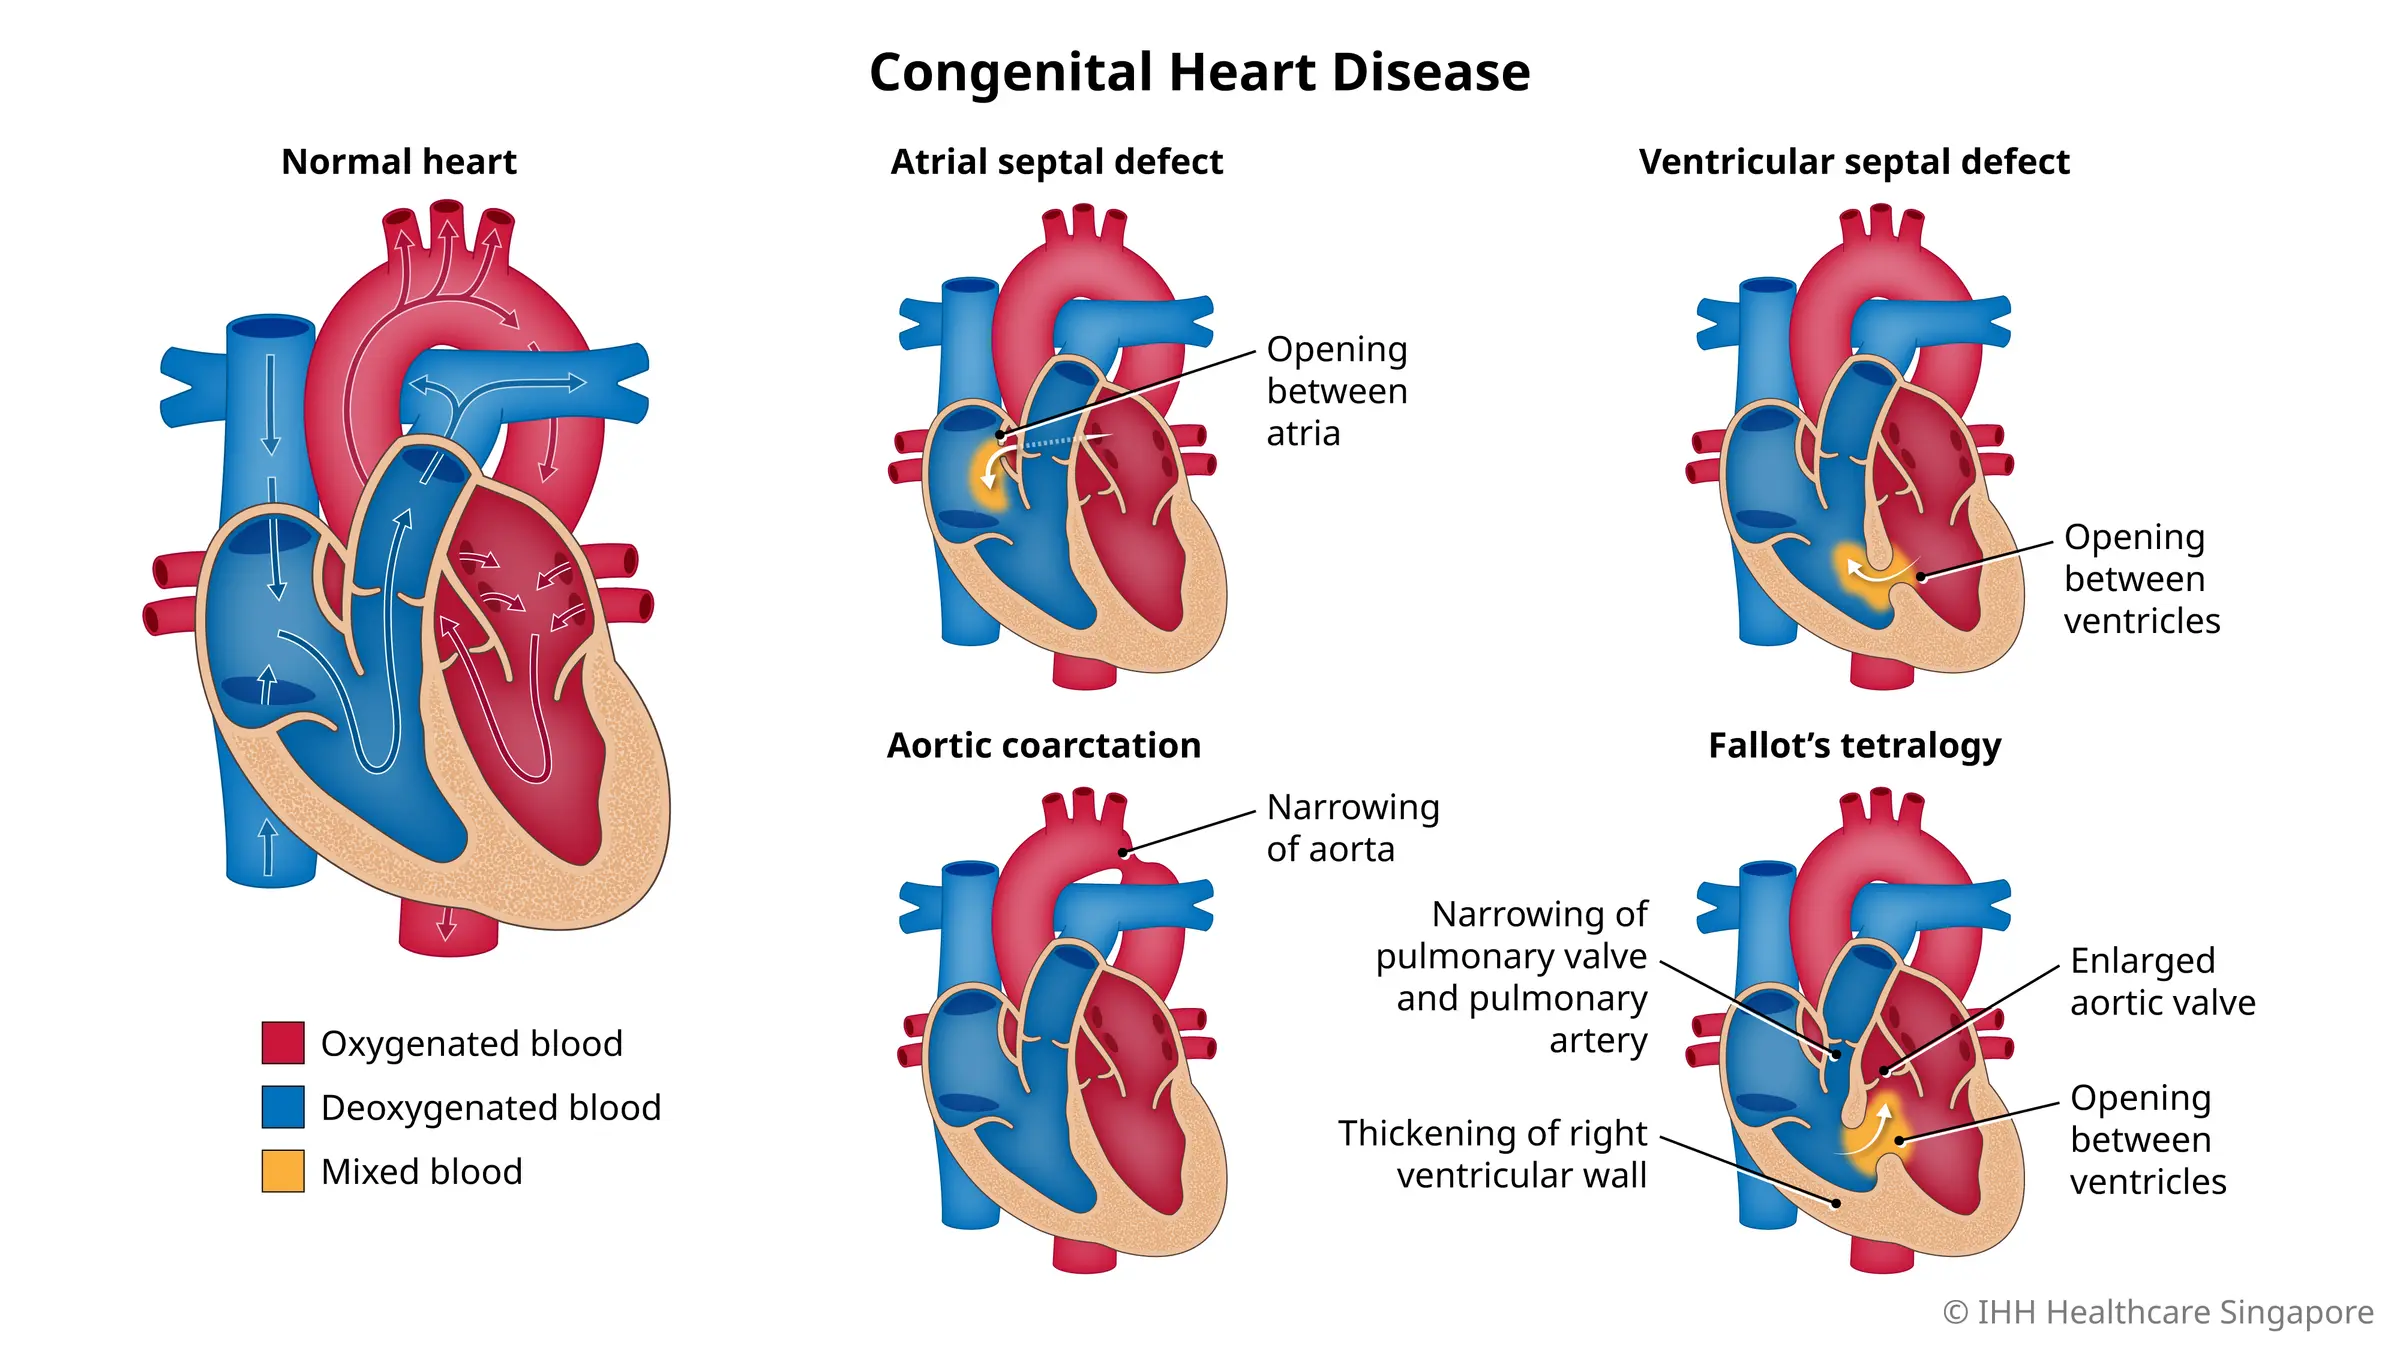

Пороки сердечно-сосудистой системы: виды и признаки